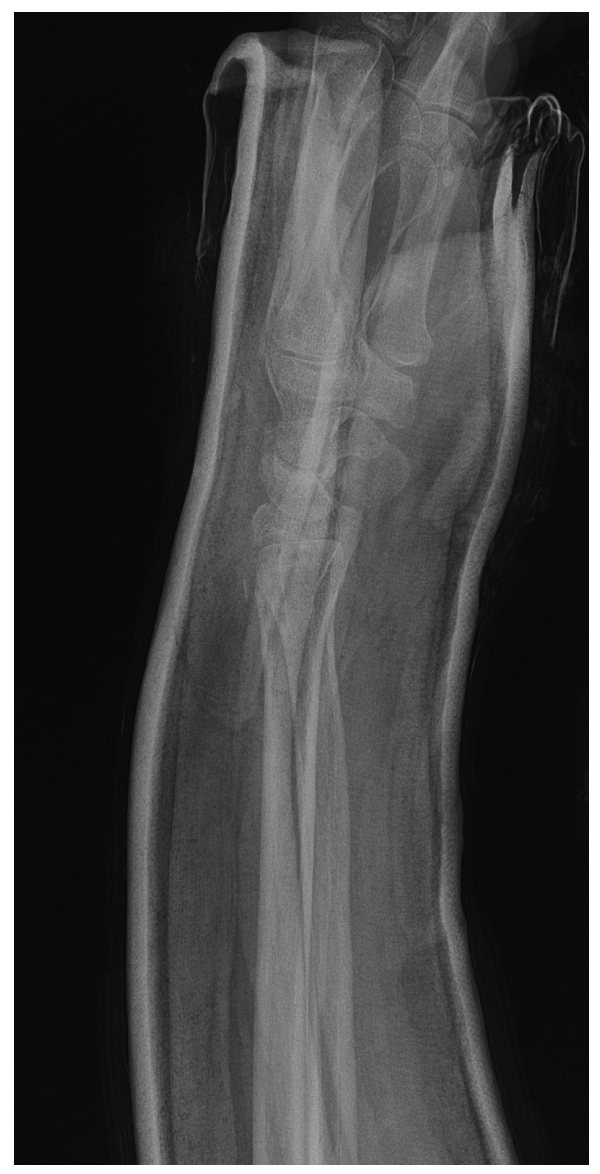

3、手法复位,术者拇指置于骨折远端,牵引恢复桡骨远端高度,手相对于桡骨远端/腕关节的掌屈和旋前有助于恢复掌倾角和尺偏角。

4、外固定,注意石膏的三点塑形(3-point mold)。上图为使用双手和大腿

对石膏进行三点塑形的两种方式。

固定位置:腕关节中立或轻度背伸,20-30度尺偏,前臂中立位

即使是Colles骨折,手掌相对于手腕的过度掌屈位固定对复位后再移位并无益处。

三点塑形后的石膏

复位过程及三点塑形